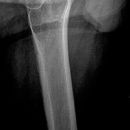

Hüfte nach Lauenstein II (15°)

Beurteilung des Schenkelhalses

Qualitätskriterien

Gute Beurteilung des Hüftkopfes, der Pfanne und des Schenkelhalses. Der Trochanter major überdeckt bei teilweise den Schenkelhals.